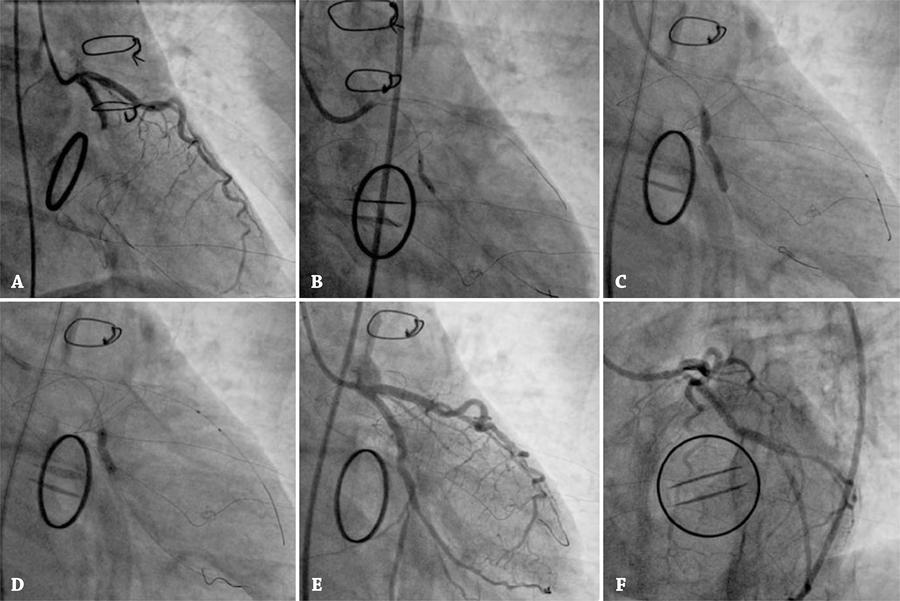

Figure 3

Immediate postoperative coronary angiography. (A) Occlusion of the left circumflex artery. (B) Pre-dilation of coronary stenosis with non-compliant balloon. (C) Bare-metal stent implanted, illustrating a waist in the balloon at the site of the stricture. (D) Post-dilatation of the stent using non-compliant balloon. (E and F) Angiographic views after the procedure.